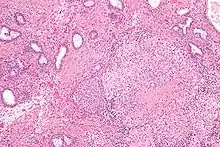

Micrograph showing granulomatous inflammation of bladder neck tissue due to Bacillus Calmette–Guérin used to treat bladder cancer, H&E stain

BCG has been one of the most successful immunotherapies.[32] BCG vaccine has been the "standard of care for patients with bladder cancer (NMIBC)" since 1977.[32][33] By 2014 there were more than eight different considered biosimilar agents or strains used for the treatment of nonmuscle-invasive bladder cancer.[32] [33]

• BCG is used in the treatment of superficial forms of bladder cancer. Since the late 1970s, evidence has become available that instillation of BCG into the bladder is an effective form of immunotherapy in this disease.[34] While the mechanism is unclear, it appears a local immune reaction is mounted against the tumor. Immunotherapy with BCG prevents recurrence in up to 67% of cases of superficial bladder cancer.